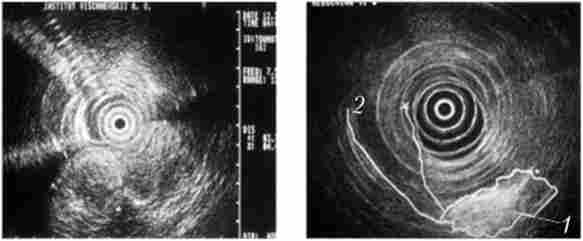

Досить достовірні дані про місцеве поширення пухлини, інвазії судин, регіонарних метастазах можуть бути отримані при використанні ендоультрасонографіі (ЕУСГ) - нового методу діагностики, ефективність якого широко обговорюється в літературі. При цьому дослідженні датчик можна підвести безпосередньо до пухлини (лапароскопично, через шлунок і ДНК, інтрадуктально через БДС, інтрапортально), що дозволяє виявити освіти менше 1 см, а при інтрадуктальном УЗД - пухлини до 2 мм, збільшені лімфатичні вузли, інвазію великих судин, виконати голкові біопсію цих утворень. Недоліком ЕУСГ виступає велика залежність результатів досліджень від досвіду лікаря, що виконує дослідження, що істотно обмежує його застосування і заважає широкому поширенню методу (рис. 21.6).

Ендоультрасонографія

Мал. 21.6. Ендоультрасонографія:

1 - пухлина головки підшлункової залози; 2 - розширений термінальний відділ загальної жовчної протоки